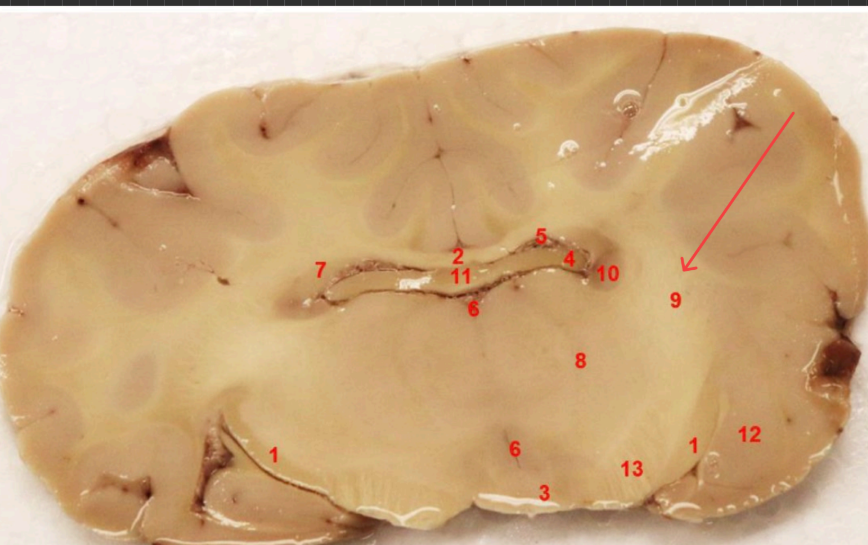

what is this

Habenula

fornix

mammillothalmic tract

what area is this

hippocampus

entorhinal cortex

subiculum

lateral geniculate nucleus, filters visual signals, mediates attention by prioritizing important information,

what is this (13)

denate gyrus

hippocampal commisure

LGN

enthorinal cortex

MGN

thalamus

posterior commissure

splenium of corpus callosum

superior colliculs

cerebral aqueduct

periaqueductal gray

superior colliculus

red nucleus

what is this, function

ventral tegmental area , brain's reward system, motivation, and emotion regulation

substaina nigra, regulates voluntary movement, motor planning, reward-seeking, and addiction

cerebral punducle

what is this, function?

dorsal raphe nucleus , serotonin, (mood, sleep, emotion)

what is this , function

locus coerules , regulating arousal, wakefulness, attention, and stress responses

dorsal raphe nucleus

superior cerebellar punudcle, inferior cerebellar punducle

what is this , function?

Reticular formation arousal, consuoiunsess, sleepwake ( keeps u awake!!!)